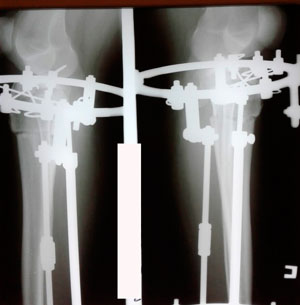

Исходник 37 лет.

Дата операции - 13.05.2020

в процессе исправления деформации